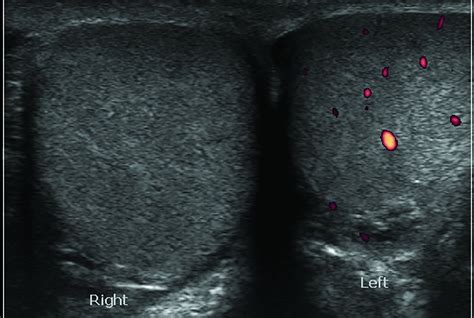

Scrotal Ultrasound (Color Doppler) Evaluating blood flow to the testicle; essential to rule out full testicular torsion.

⚠️ Note: If there is any clinical ambiguity or if the blood flow to the testicle itself appears compromised on ultrasound, an emergency surgical exploration (orchiopexy) is performed to rule out testicular torsion.